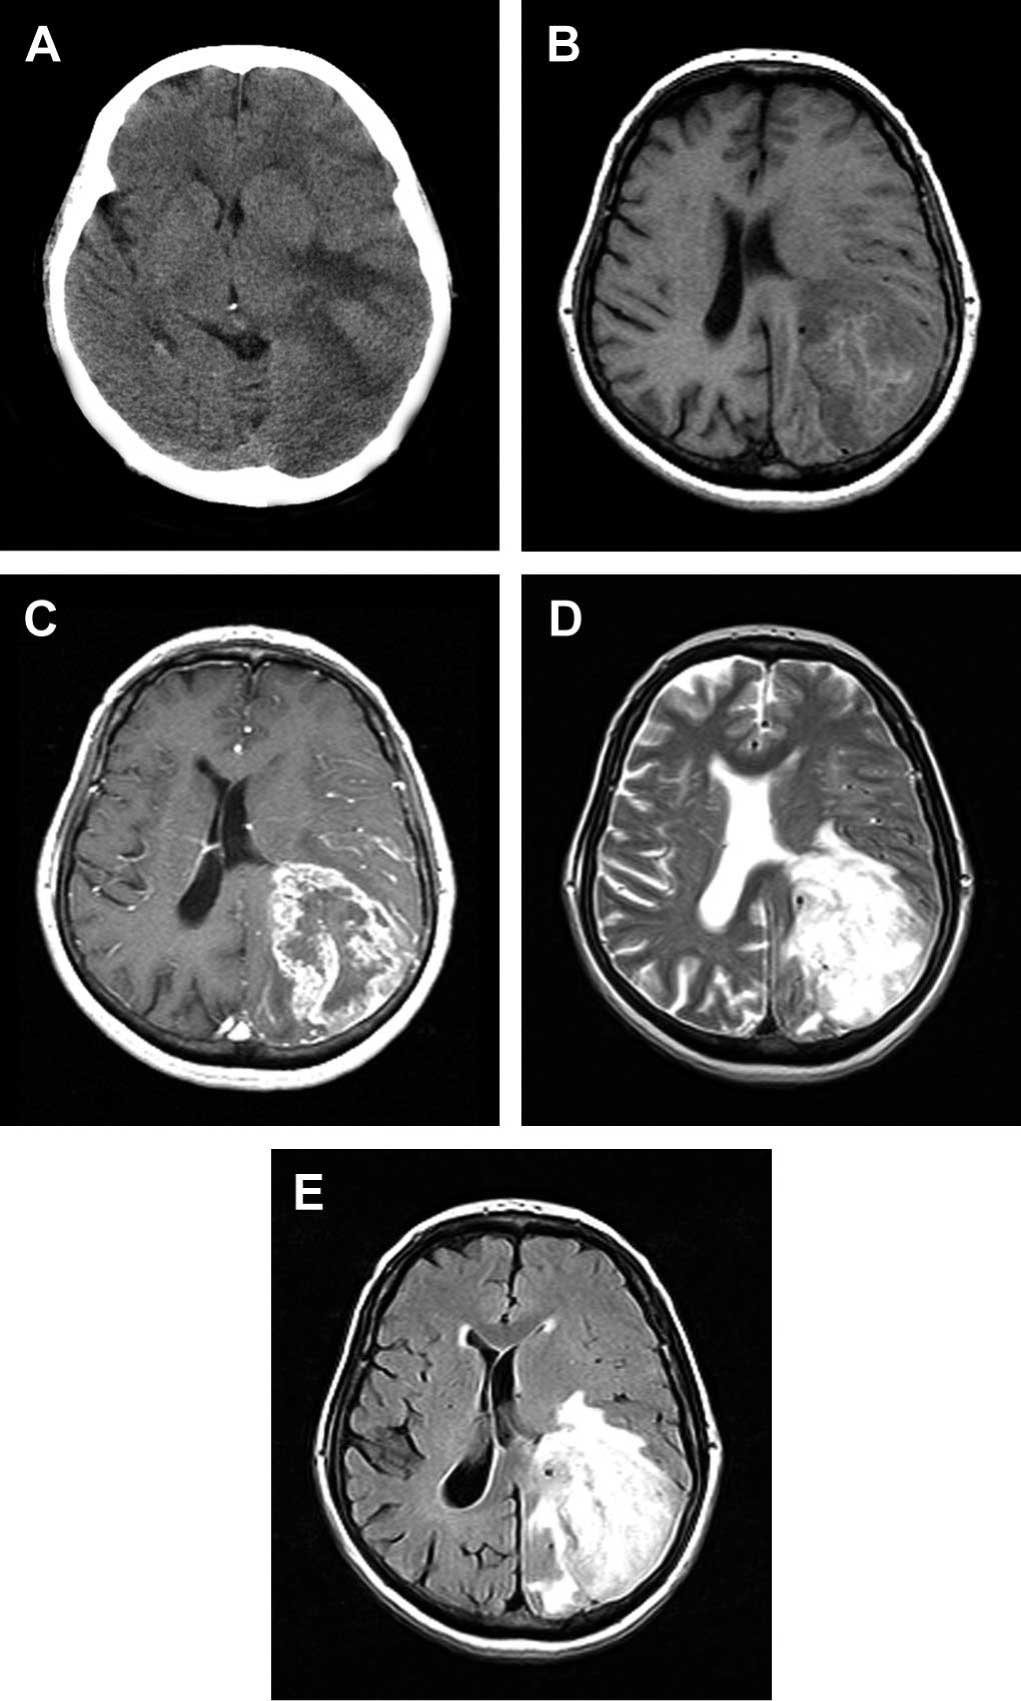

Якщо у вас є підозри щодо набряку головного мозку, негайно потрібно проконсультуватися з лікарем. Діагностика цього стану включає:

- Комп’ютерну томографію (КТ) голови.

- Магнітно-резонансну томографію (МРТ).